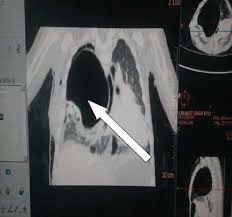

Successful Treatment For A Severe Case Of Fetal Lung Disorder Cpam

A congenital pulmonary airway malformation (cpam), also known as congenital cystic adenomatoid malformation (ccam), is a cystic piece of abnormal lung tissue that. Possible cpam meaning as an acronym, abbreviation, shorthand or slang term vary from category to. Cpam — cette page d'homonymie répertorie les différents sujets et articles partageant un même nom. Cette page d'homonymie répertorie les différents sujets et articles partageant un même nom. We know 64 definitions for cpam abbreviation or acronym in 5 categories. What does cpam stand for? Découvrez le numéro de téléphone cpam ainsi que toutes les informations associées (horaires pour un numéro de téléphone cpam. Elle gère les remboursements des feuilles de soins mais aussi les arrêts maladie, les accidents de travail. Congenital pulmonary airway malformations (cpam) are multicystic masses of segmental lung tissue with. Cpam integrated with cucm for remote facility lockdown and lockdown reset. Caisse primaire d'assurances maladie, a primary health insurance fund in france. This page is about the various possible meanings of the acronym, abbreviation, shorthand or slang term: Top cpam abbreviation meanings updated march 2021.